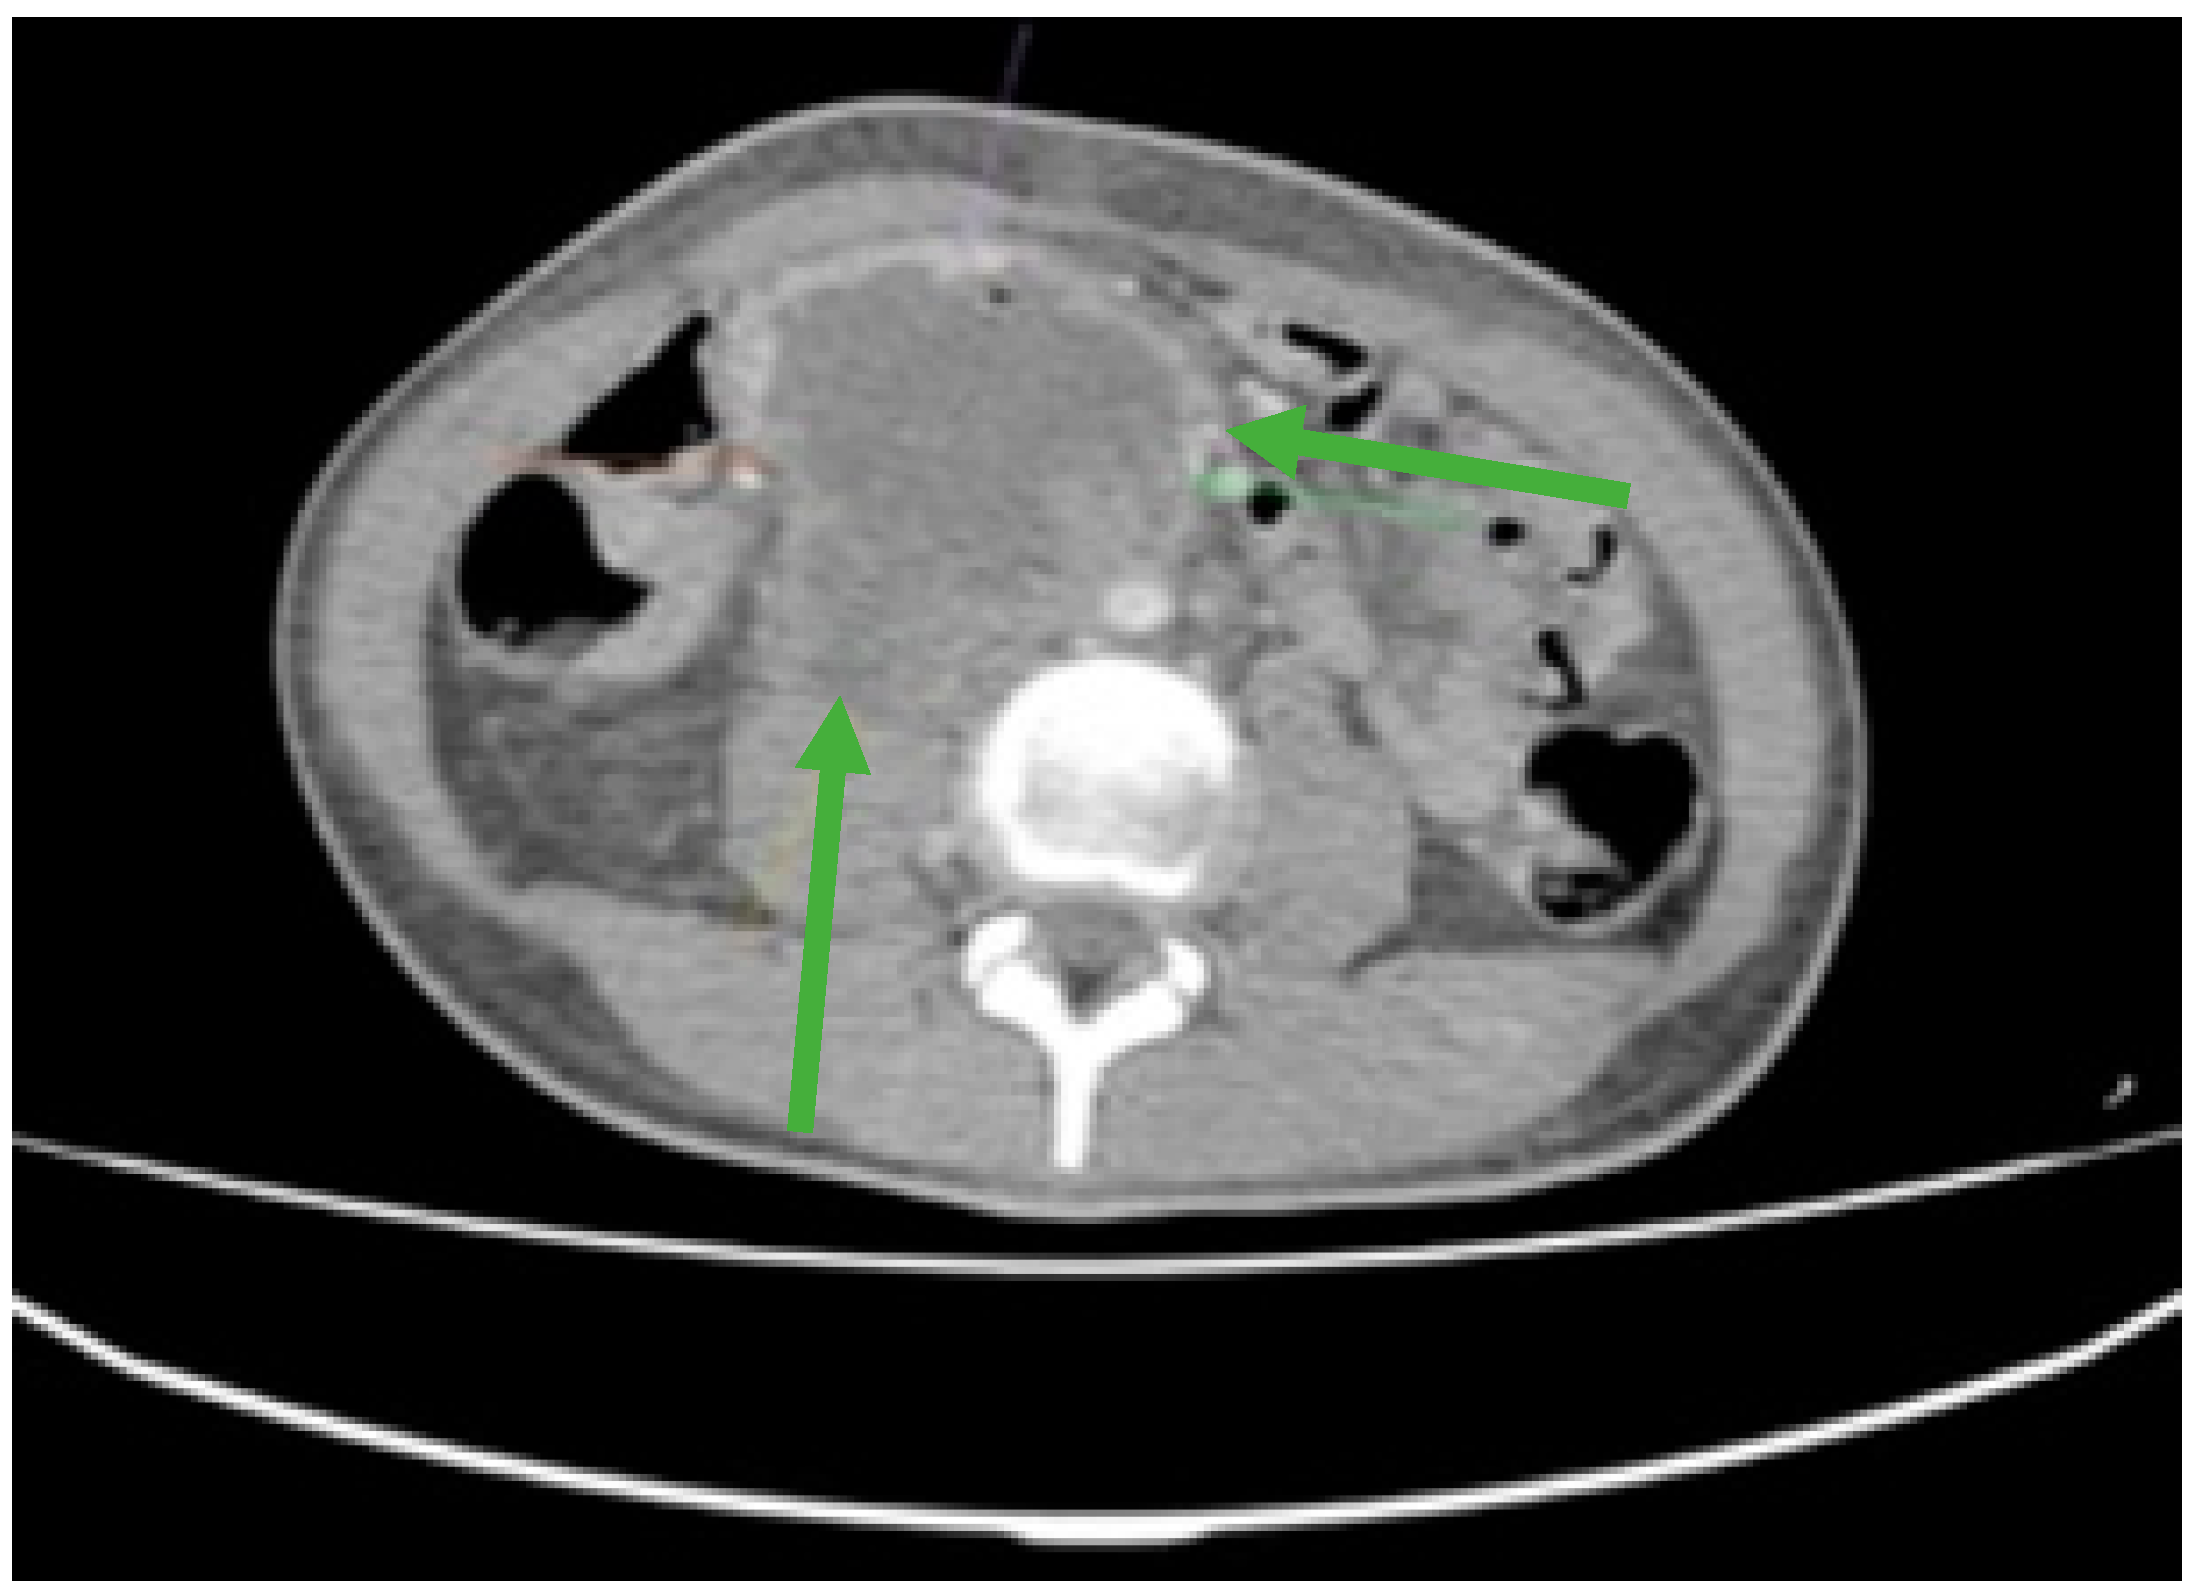

Figure 4.

CT scan showing liver metastases in numerical and dimensional progression (green arrows).

During the maintenance therapy with oral etoposide, the plasma beta HCG was highly increased (6228 mIU/mL), so we decided to start third line chemotherapy with GOP (gemcitabine 800 mg/sqm day 1 and 8, paclitaxel 80 mg/sqm day 1 and 8, oxaliplatin 130 mg day 1, q3w). After five cycles, we observed a new biological and imagistic progression (Figure 3 and Figure 4) in the size and number of the liver and lung metastases that appeared.